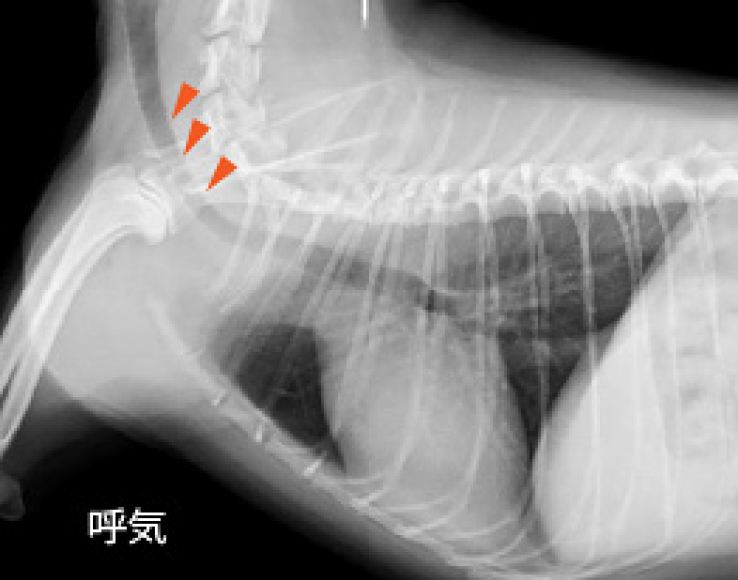

レントゲン検査によって肺や気管の状態を確認することができます。肺野の病変の画像パターンを分類し、どのような疾患が疑わしいのか診断することができます。また、吸気時と呼気時のレントゲン写真を撮ることによって、気管虚脱の有無を診断することができます。当院では、単純なレントゲン撮影では判断の難しい気管虚脱に対しても透視下のレントゲン撮影が可能であり、動的に気管虚脱を診断することができます。超音波検査は、胸水や腫瘤の診断に役立ちます。また、呼吸器症状の原因となりうる心臓疾患の存在を診断することができます。

気管虚脱

トイ犬種、小型犬、および肥満犬に多い病気です。「ガーガー」というガチョウの鳴き声の様な咳をするのが特徴です。正常な気管は軟骨によって支えられていますが、気管虚脱では軟骨の変性に伴い気管が潰れるため、呼吸困難になってしまいます。気管の潰れ方が大きいほど症状も重篤になります。気管虚脱は進行していくため、症状が軽いうちに診断し軟骨の保護を行うことや、体重を適正に管理することで進行を抑えることができると考えられています。